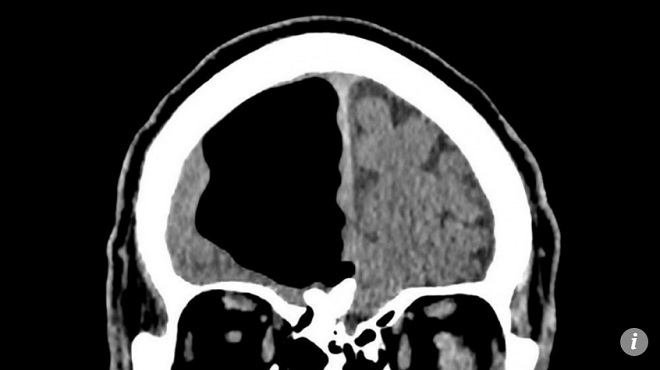

Khoảng trống khổng lồ bên trong não bệnh nhân.

Nói cách khác, các bác sĩ không nhận thấy điều gì bất thường, cho đến khi đưa bệnh nhân đi chụp CT và MRI. Đó là lúc các bác sĩ cảm thấy kinh ngạc khi trong đầu bệnh nhân có một khoảng trống lớn, dường như là do bóng khí hình thành. Khu vực này lẽ ra là nơi chứa thùy não phải của bệnh nhân.

Khoảng trồng thực chất là bong bóng khí chèn ép thùy não phải.

Bệnh nhân chưa từng trải qua bất kỳ một ca phẫu thuật não nào. Khoảng trống lớn trong đầu bệnh nhân dài tới 8,9cm, chứa toàn không khí.